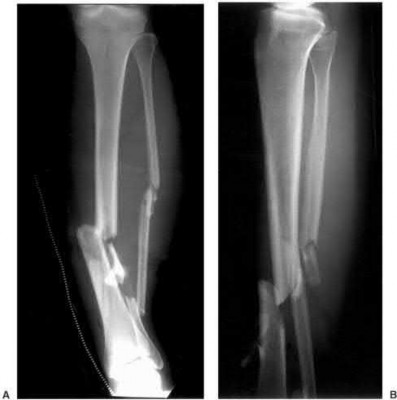

Question 3:

A 15-year-old boy presents with a permeative lytic lesion in the femoral diaphysis with aggressive periosteal reaction ('onion skinning'). Biopsy reveals uniform small round blue cells. Cytogenetic analysis of this tumor will most likely demonstrate which of the following translocations?

Options:

- t(11;22)

- t(9;22)

- t(2;13)

- t(X;18)

- t(12;16)

Correct Answer: t(11;22)

Explanation:

The clinical and radiographic description is classic for Ewing sarcoma. The characteristic cytogenetic abnormality is a balanced translocation t(11;22)(q24;q12), which fuses the EWS gene on chromosome 22 with the FLI1 gene on chromosome 11. This is seen in approximately 85-90% of Ewing sarcomas. t(9;22) is the Philadelphia chromosome (CML), t(X;18) is seen in synovial sarcoma, t(2;13) in alveolar rhabdomyosarcoma, and t(12;16) in myxoid liposarcoma.